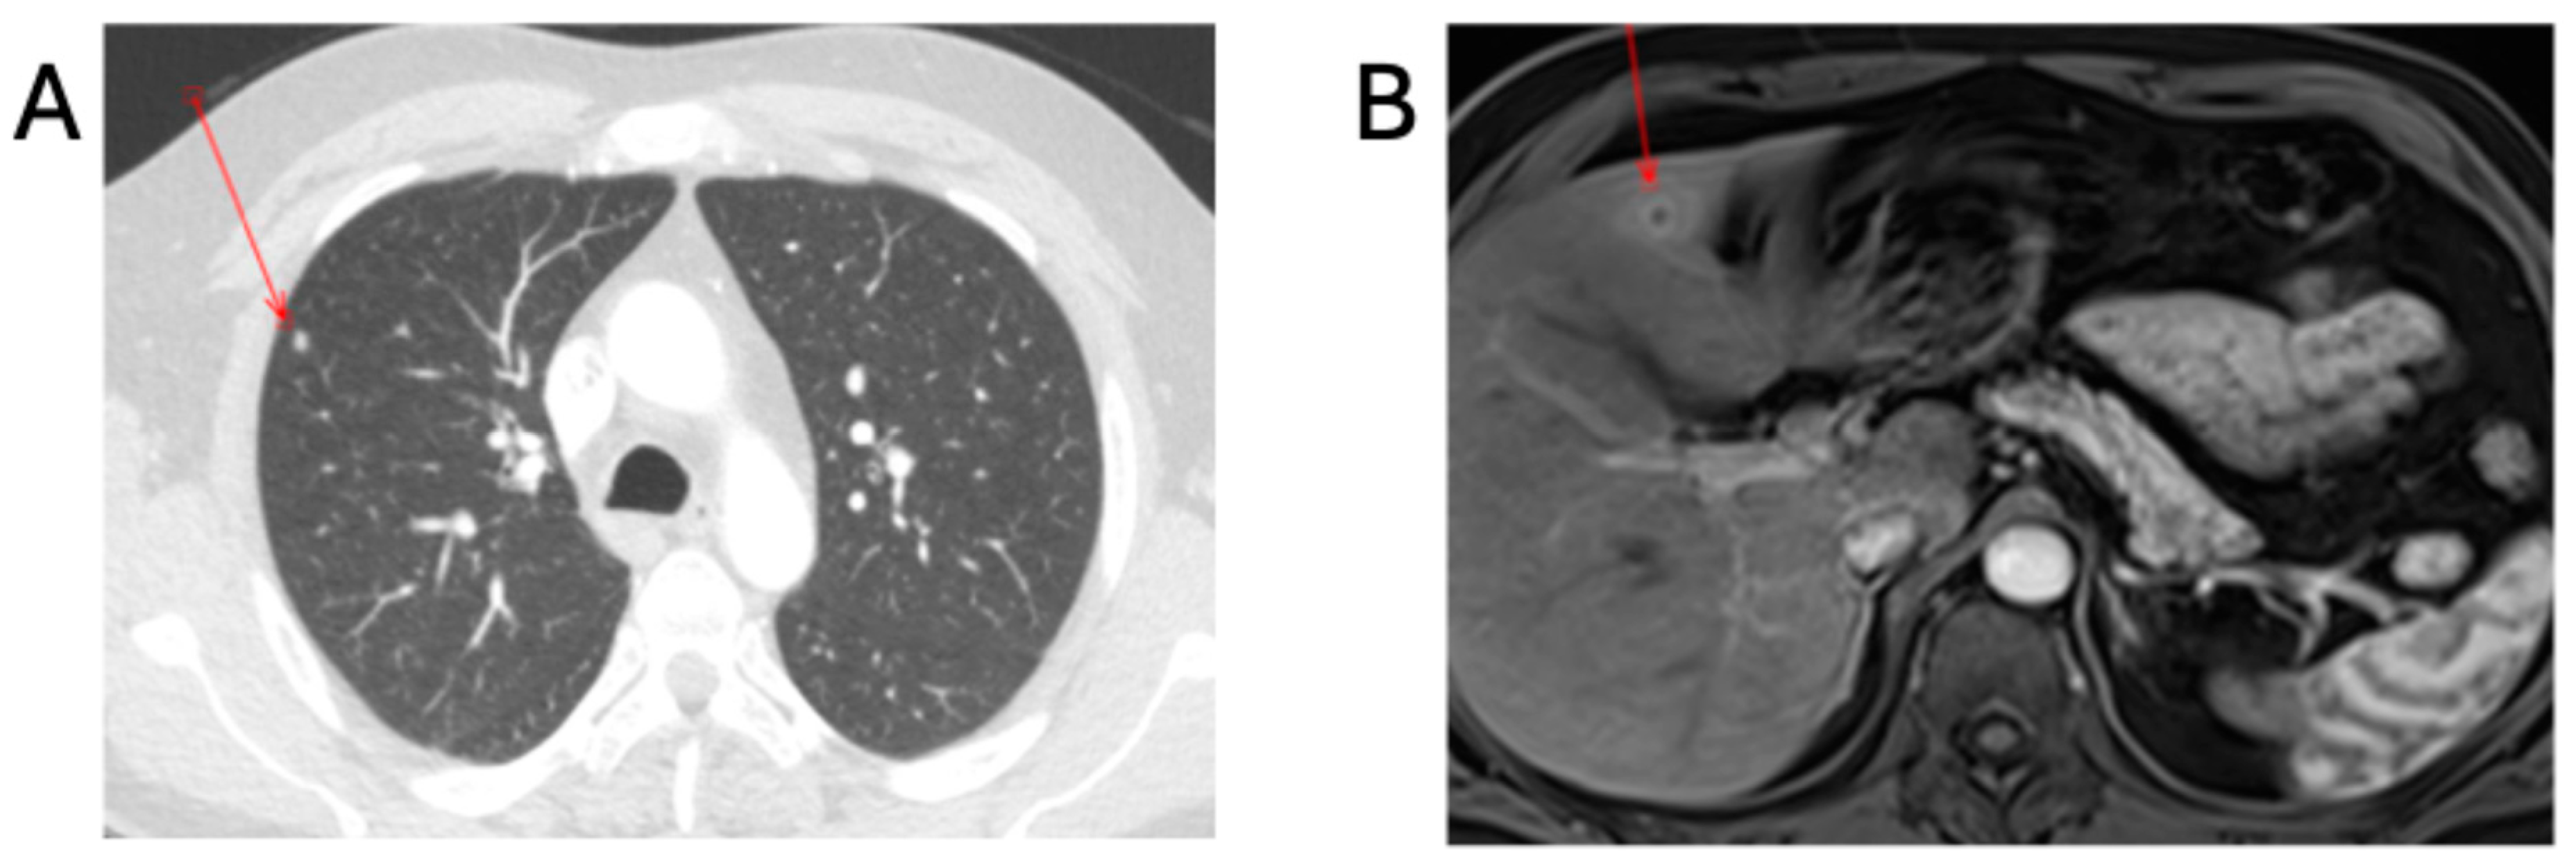

Further investigations to exclude complicated disease consisted of a transthoracic echocardiogram (TTE) and contrast-enhanced computed-tomography scan of the thorax, abdomen and pelvis (CT-TAP). The TTE was negative, and the CT-TAP showed a 6 mm hypodensity within hepatic segment IV, presenting as an abscess and hyper-enhanced gallbladder walls with fat stranding, suggesting cholecystitis; periportal, pericaval, pericardial, and intrapulmonary lymphadenopathy; and two 5 mm pulmonary nodules in the right upper and lower lobes (Figure 2). Combination antibiotic therapy commenced, consisting of intravenous IV gentamicin at 5 mg/kg once a day and 100 mg oral doxycycline twice a day.

Figure 2. Radiological findings in patient A. (A) CT-TAP with contrast showing 5 mm right upper lobe non-specific pulmonary nodule. (B) MRI liver with contrast showing 12 mm hepatic abscess in left lobe. The red arrows demonstrate the lesions.